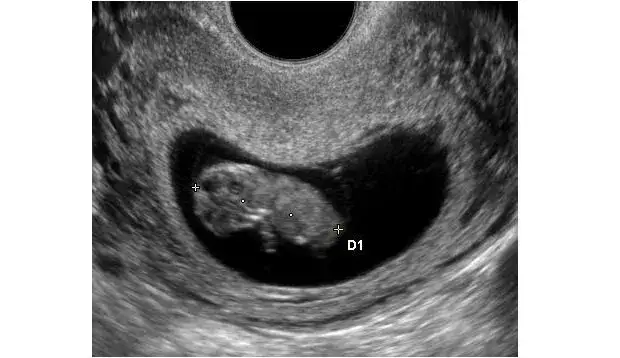

Badanie ultrasonograficzne jest jedną z najczęściej stosowanych metod do określenia płci dziecka. Działa na zasadzie emitowania fal dźwiękowych, które tworzą obraz płodu. Właściwe ułożenie płodu oraz jakość sprzętu mają kluczowe znaczenie dla dokładności tego badania. Zwykle lekarze są w stanie określić płeć między 18. a 22. tygodniem ciąży, chociaż w niektórych przypadkach możliwe jest to już od 12. tygodnia. Warto jednak pamiętać, że wcześniejsze badania mogą być mniej precyzyjne, ponieważ narządy płciowe mogą być jeszcze niedorozwinięte.Badanie ultrasonograficzne jest jedną z najczęściej stosowanych metod do określenia płci dziecka. Działa na zasadzie emitowania fal dźwiękowych, które tworzą obraz płodu. Właściwe ułożenie płodu oraz jakość sprzętu mają kluczowe znaczenie dla dokładności tego badania. Zwykle lekarze są w stanie określić płeć między 18. a 22. tygodniem ciąży, chociaż w niektórych przypadkach możliwe jest to już od 12. tygodnia. Warto jednak pamiętać, że wcześniejsze badania mogą być mniej precyzyjne, ponieważ narządy płciowe mogą być jeszcze niedorozwinięte.| Metoda | Dokładność | Termin wykonania |

Wybór odpowiedniego terminu na wykonanie badań w celu określenia płci dziecka jest kluczowy. Badanie ultrasonograficzne zazwyczaj wykonuje się między 18. a 22. tygodniem ciąży, co pozwala na uzyskanie najbardziej wiarygodnych wyników. W niektórych przypadkach, dzięki doświadczeniu lekarza i jakości sprzętu, możliwe jest ustalenie płci już w 12. tygodniu, ale wtedy dokładność może być niższa. Alternatywnie, genetyczne testy prenatalne (NIPT) można przeprowadzić już od 10. tygodnia ciąży, co czyni je jedną z pierwszych opcji dostępnych dla rodziców.